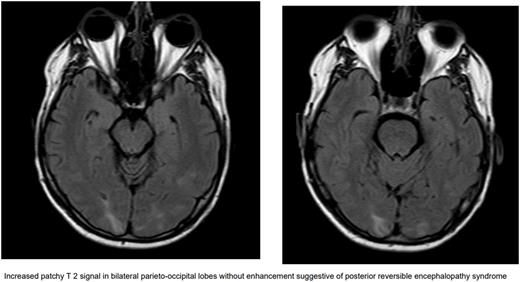

Case Presentation: A 52-year-old male with no significant past medical history presented to the hospital with left sided numbness and spatial recognition issues. A computed tomography (CT) of the head revealed a 3 cm right parietal mass with vasogenic edema later confirmed with a magnetic resonance imaging (MRI) of the brain. He was started on steroids along with 500 mg Keppra twice a day. CT of the chest, abdomen, and pelvis showed multiple hepatic masses and retroperitoneal lymphadenopathy. He had a colonoscopy about a year prior that was unremarkable. He underwent right frontal parietal craniotomy for single brain metastatic lesion. The biopsy of both the brain and liver mass revealed metastatic adenocarcinoma. He was discharged and started on Fluorouracil, Folinic Acid, Oxaliplatin (FOLFOX) chemotherapy as outpatient for possible upper gastrointestinal (GI) cancer. After two cycles of chemotherapy, a positron emission tomography (PET) scan revealed suspected primary esophageal cancer. Though patient had zero PDL-1 biomarker, nivolumab was added to cycle 3 of FOLFOX with the expectation of having a better response early in the disease. He continued to have stereotactic radiosurgery (SRS) along with steroid taper for local control of brain metastasis. Nivolumab was held after cycle 2 as he developed mild headache, fever and elevated lipases. He was found to be hypertensive to 144/85 mmHg. MRI brain showed improving post-surgical changes. On improvement of symptoms, Nivolumab was reintroduced to cycle 6 of FOLFOX. Unfortunately, a week later he developed progressive vision loss more on right eye. He was sent to optometrist who referred patient to emergency room (ER) because of concern for bilateral papilledema. On admission to ER, he was hypertensive to 182/104 and tachycardic to 107 beats per minute. Physical exam was significant for left inferior quadrantanopia more prominent in right eye. CT head was unrevealing for any infarct. MRI of the orbit and brain showed increased patchy T 2 signal in bilateral parieto-occipital lobes without enhancement suggestive of posterior reversible encephalopathy syndrome (PRES) along with right optic neuritis. These findings were attributed to the immunotherapy nivolumab. He was started on a high dose of prednisone, 1mg/kg/day along with 20 mg lisinopril for strict blood pressure control with a goal of 120/80 mmHg. He was discharged with tapering steroids dose and his symptoms improved within 1 week of treatment.

Discussion: Posterior reversible encephalopathy syndrome is a clinico-radiological diagnosis. The underlying pathophysiology involves hypertension and endothelial dysfunction. Hypertension leads to cerebral hyper-perfusion which may cause vascular damage and vasogenic edema leading to blood brain barrier dysfunction. The posterior circulation is the most susceptible to blood pressure changes, thus it is the most common imaging abnormality. PRES frequently develops in the context of cytotoxic medication, immunotherapy, (pre)eclampsia, sepsis, renal disease or autoimmune disorders. MRI is an important diagnostic tool and displays hyperintense lesions in T2-weighted or FLAIR sequences in the parietal-occipital lobes in about 70% of cases but other parts can also be involved. Electroencephalogram (EEG) and lumbar puncture (LP) can be done to rule out other causes. Differentiation is important from an ischemic event as management is different in both cases. Treatment of PRES is symptomatic. Recommendations are to avoid fluctuations in blood pressure with a goal of 130-150/80-100mmHg. If any triggering factor or condition is identified like immunotherapy, it should be avoided or treated accordingly.